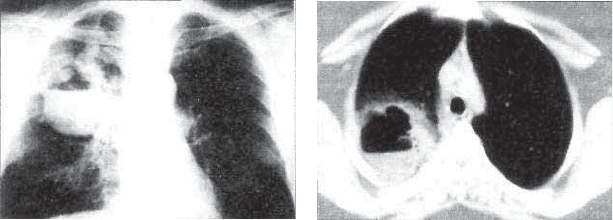

изменений. Среди фиброзной ткани определяются казеозные

очаги. Могут быть обнаружены и остаточные щелевидные ка-

верны с фиброзными стенками (рис. 15.2). Грубая деформа-